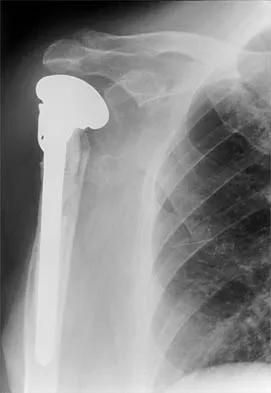

A 62-year-old man with a long history of right shoulder pain and weakness is scheduled to undergo hemiarthroplasty. Based on the radiographs shown in Figures 6a through 6c, what preoperative factor will most affect postoperative functional outcome?

Explanation

The radiographs reveal osteoarthritis and proximal humeral head migration. Integrity of the rotator cuff must be questioned based on these radiographic changes. The status of the rotator cuff is the most influential factor affecting postoperative function in shoulder hemiarthroplasty. The coracoacromial ligament provides a barrier to humeral head proximal migration in the face of a rotator cuff tear. The radiographs do not indicate significant humeral head or glenoid erosion. Acromioclavicular arthritis is often asymptomatic. Iannotti JP, Norris TR: Influence of preoperative factors on outcome of shoulder arthroplasty for glenohumeral osteoarthritis. J Bone Joint Surg Am 2003;85:251-258.